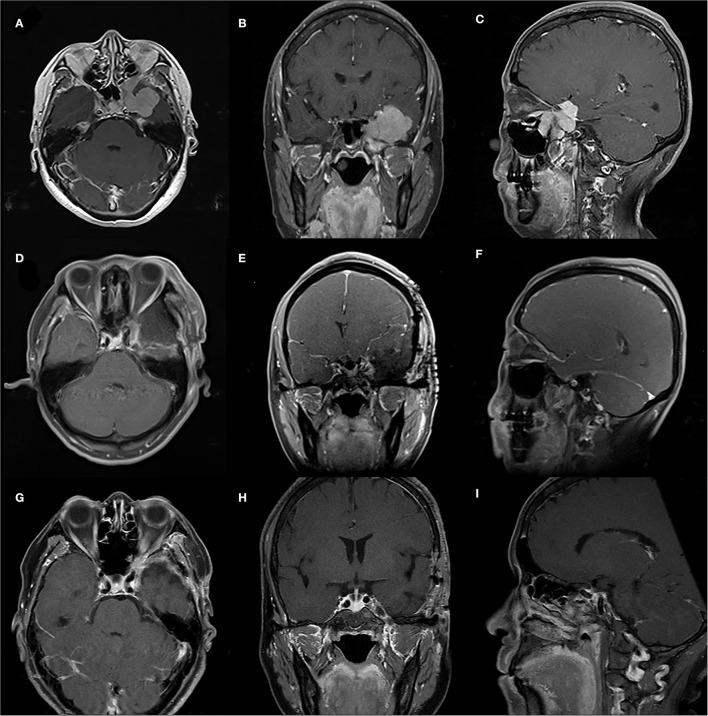

颅底脑膜瘤伴颅外扩展的管理:临床特征、影像学表现、手术策略及长期预后

Management of Skull-Base Meningiomas With Extracranial Extensions: Clinical Features, Radiological Findings, Surgical Strategies, and Long-Term Outcomes.

The incidence of skull-base meningiomas with extracranial extensions was 0.74%. The average diagnosis age was 45.9 years, with a 1:3.1 men to women ratio. WHO grade I was seen in 84.9% of patients, and higher grades were found in 15.1%. Heterogeneous enhancement, high bone invasion rate, high incidence of peritumoral edema, and high dural tail sign rate were typical imaging features. Routine craniotomy and endoscopic endonasal approach were adopted, and gross total resection was performed in 62.3% of cases with 20.8% postoperative complication rates. The average follow-up time was 61.5 months, with a recurrence rate of 34.9%. By survival analysis, the extent of resection ( = 0.009) and the histological grade ( = 0.007) were significantly related to the prognosis. Adjuvant radiotherapy proved beneficial in patients with subtotal resection ( = 0.010) and high-grade meningiomas ( = 0.018).

颅底脑膜瘤伴颅外扩展的发生率为0.74%。平均诊断年龄为45.9岁,男女比例为1:3.1。84.9%的患者为世界卫生组织I级,15.1%为更高等级。不均匀强化、高骨质侵犯率、瘤周水肿发生率高及硬脑膜尾征发生率高是典型的影像学特征。采用常规开颅手术和内镜鼻内入路,62.3%的病例实现了肿瘤全切除,术后并发症发生率为20.8%。平均随访时间为61.5个月,复发率为34.9%。通过生存分析,切除范围(P = 0.009)和组织学分级(P = 0.007)与预后显著相关。辅助放疗对次全切除患者(P = 0.010)和高级别脑膜瘤患者(P = 0.018)有益。